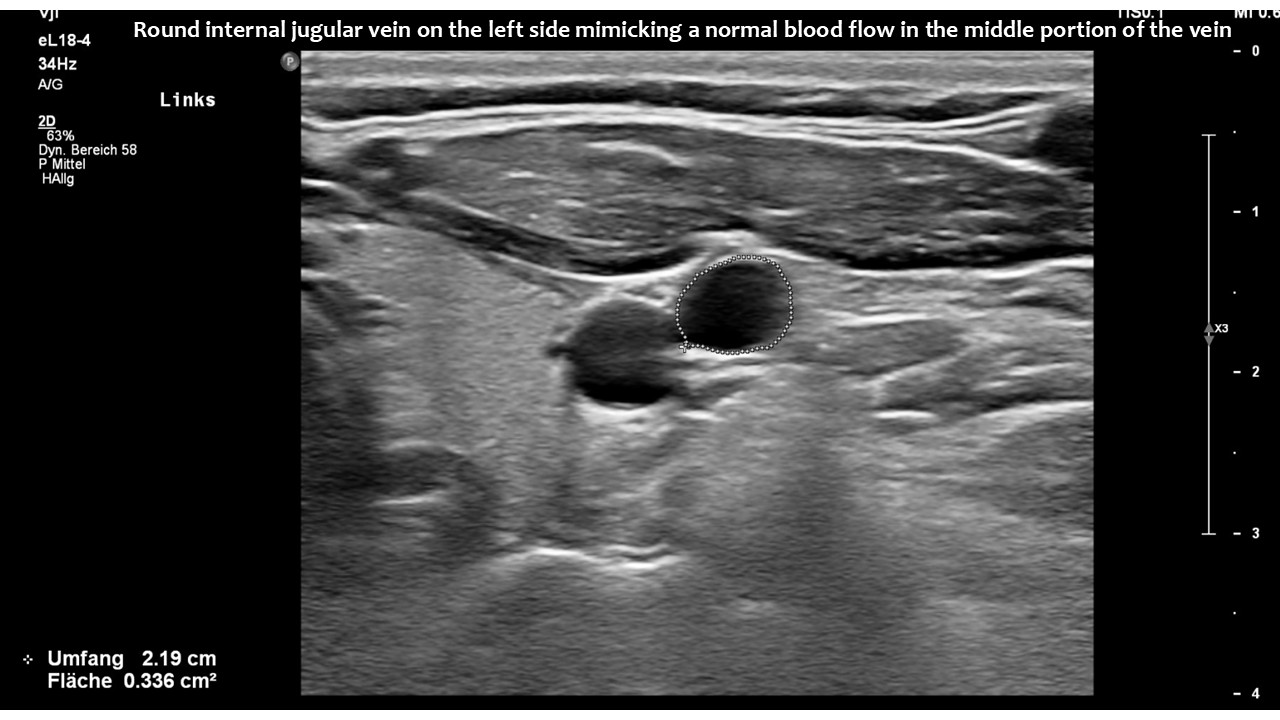

However, in this patient, both jugular veins were compressed. The middle portion of the internal jugular vein was pushed ventrally by the increased cervical lordosis on both sides, becoming squeezed between the carotid artery and the sternocleidomastoid muscle.

Consequently, blood had difficulty leaving the skull, resulting in continuously increased pressure and severe headaches, as well as other neurological dysfunction. The left side was more affected due to the double compression. This was clearly demonstrated by four-dimensional volume flow measurements in both jugular veins.

Only a four-dimensional volume flow measurement of the jugular veins can determine the cause of the daily headaches. The overall reduction in venous outflow from the brain in both jugular veins, totalling 258 mL/min, is significantly lower than the normal average volume of 719 mL/min. Consequently, the patient can eliminate only 36% of the required flow volume, while additional volume is forced into the skull from the left renal vein via the tronc réno-rachidien and from the left common iliac vein via the left ascending lumbar vein. This results in a chronic increase in intracranial pressure, as demonstrated by the elevated cerebrospinal fluid pressure obtained through a lumbar puncture. When the left jugular vein is also completely compressed due to increasing cervical lordosis when upright, the headaches become unbearable, accompanied by additional neurological symptoms as described by the patient.